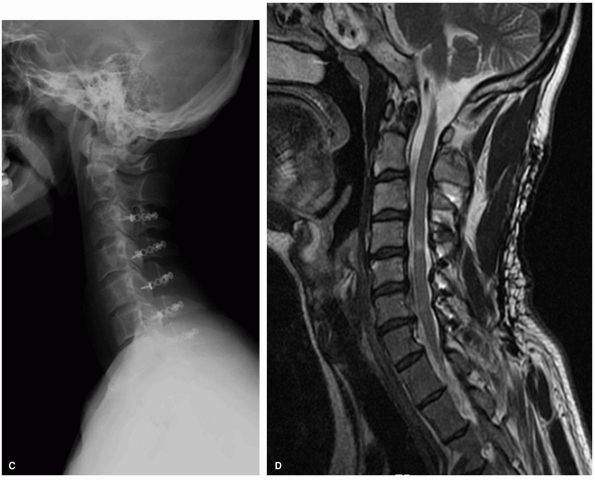

![]() |

FIGURE 11-9.

Lateral plain radiographs and sagittal T2 MRI in a patient with multilevel congenital cervical stenosis with associated spondylosis causing severe cord compression, including signal change within the cord, in a patient with spastic gait and clumsy hand consistent with cervical myelopathy (A, B). Because of the multilevel nature of the problems the treatment selected was a posterior laminoplasty with excellent recovery of neurological complaints (C, D). |

FIGURE 11-9. (Continued)

|